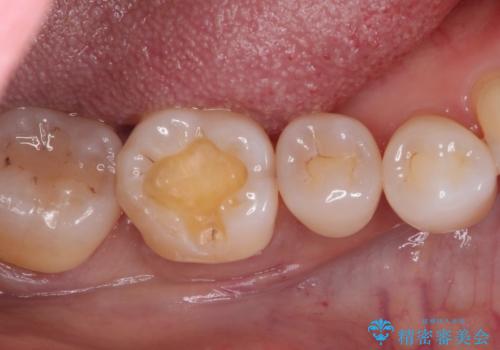

- 以前治療した歯が欠けたことを主訴に来院されました。

見た目もよく強度の高いものでの修復を希望されましたのでセラミックインレーにて修復しました。

当院でのセラミックインレーは歯とのつなぎ目を拡大鏡で確認して精度高く仕上げるため、むし歯のリスクを限りなく少なくできるよう治療します。